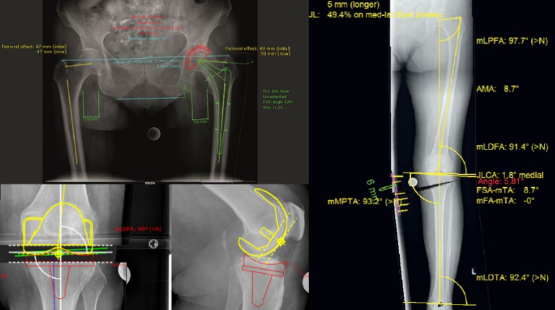

「mediCAD」術前計画作図例

「mediCAD」術前計画作図例

(東陽テクニカ展示)チュートリアル動画に従うだけで、人工関節置換術や膝周囲骨切り術などの術前計画をワークフローに沿って実施できるソフトウェアである。人工関節置換術の術前計画では、100社以上のインプラントメーカーの人工関節テンプレートデータから即座に目的の データを選択することができる。